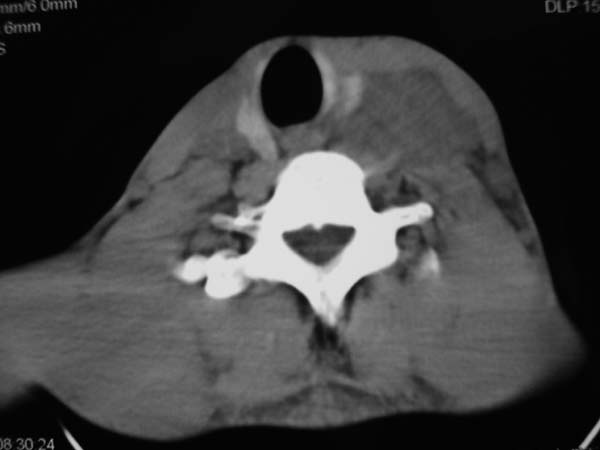

患者男性,37岁,农民,自觉左颈部肿大三天,无其它不适。

左侧颈部软组织密度肿块,界限清楚,形态不规则,占位效应明显。考虑:1 淋巴瘤。2 神经源性肿瘤不除外。

左颈部占位,病灶沿间隙分布,密度混浊,结合病史肿大三天,考虑1,炎症病变,建议增强。2,颈部血管性病变。

患者没有任何症状,炎性和淋巴瘤可能不是,主要是来源,有没有来自甲状旁腺的可能?

同甲状腺间有脂肪间隙存在,考虑不是来源于甲状腺,肿大淋巴结?

左侧甲状腺在那? 病变来自甲状腺吧,甲状腺肿或腺瘤

病灶边界较清,密度不均,其内可见坏死灶,左侧甲状腺受压,考虑神经源性肿瘤可能性大,建议穿刺活检。